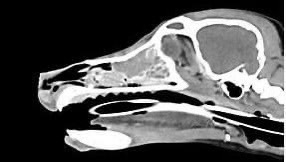

• 鼻上皮細胞癌

鼻上皮細胞癌